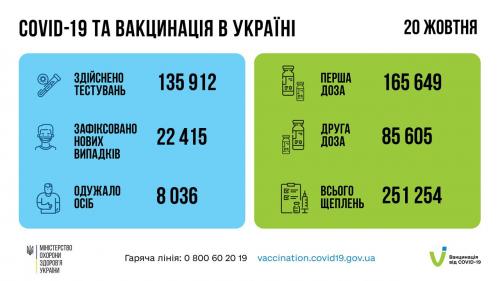

МОЗ: Уперше з початку пандемії було зроблено понад 100 тисяч ПЛР-досліджень за добу